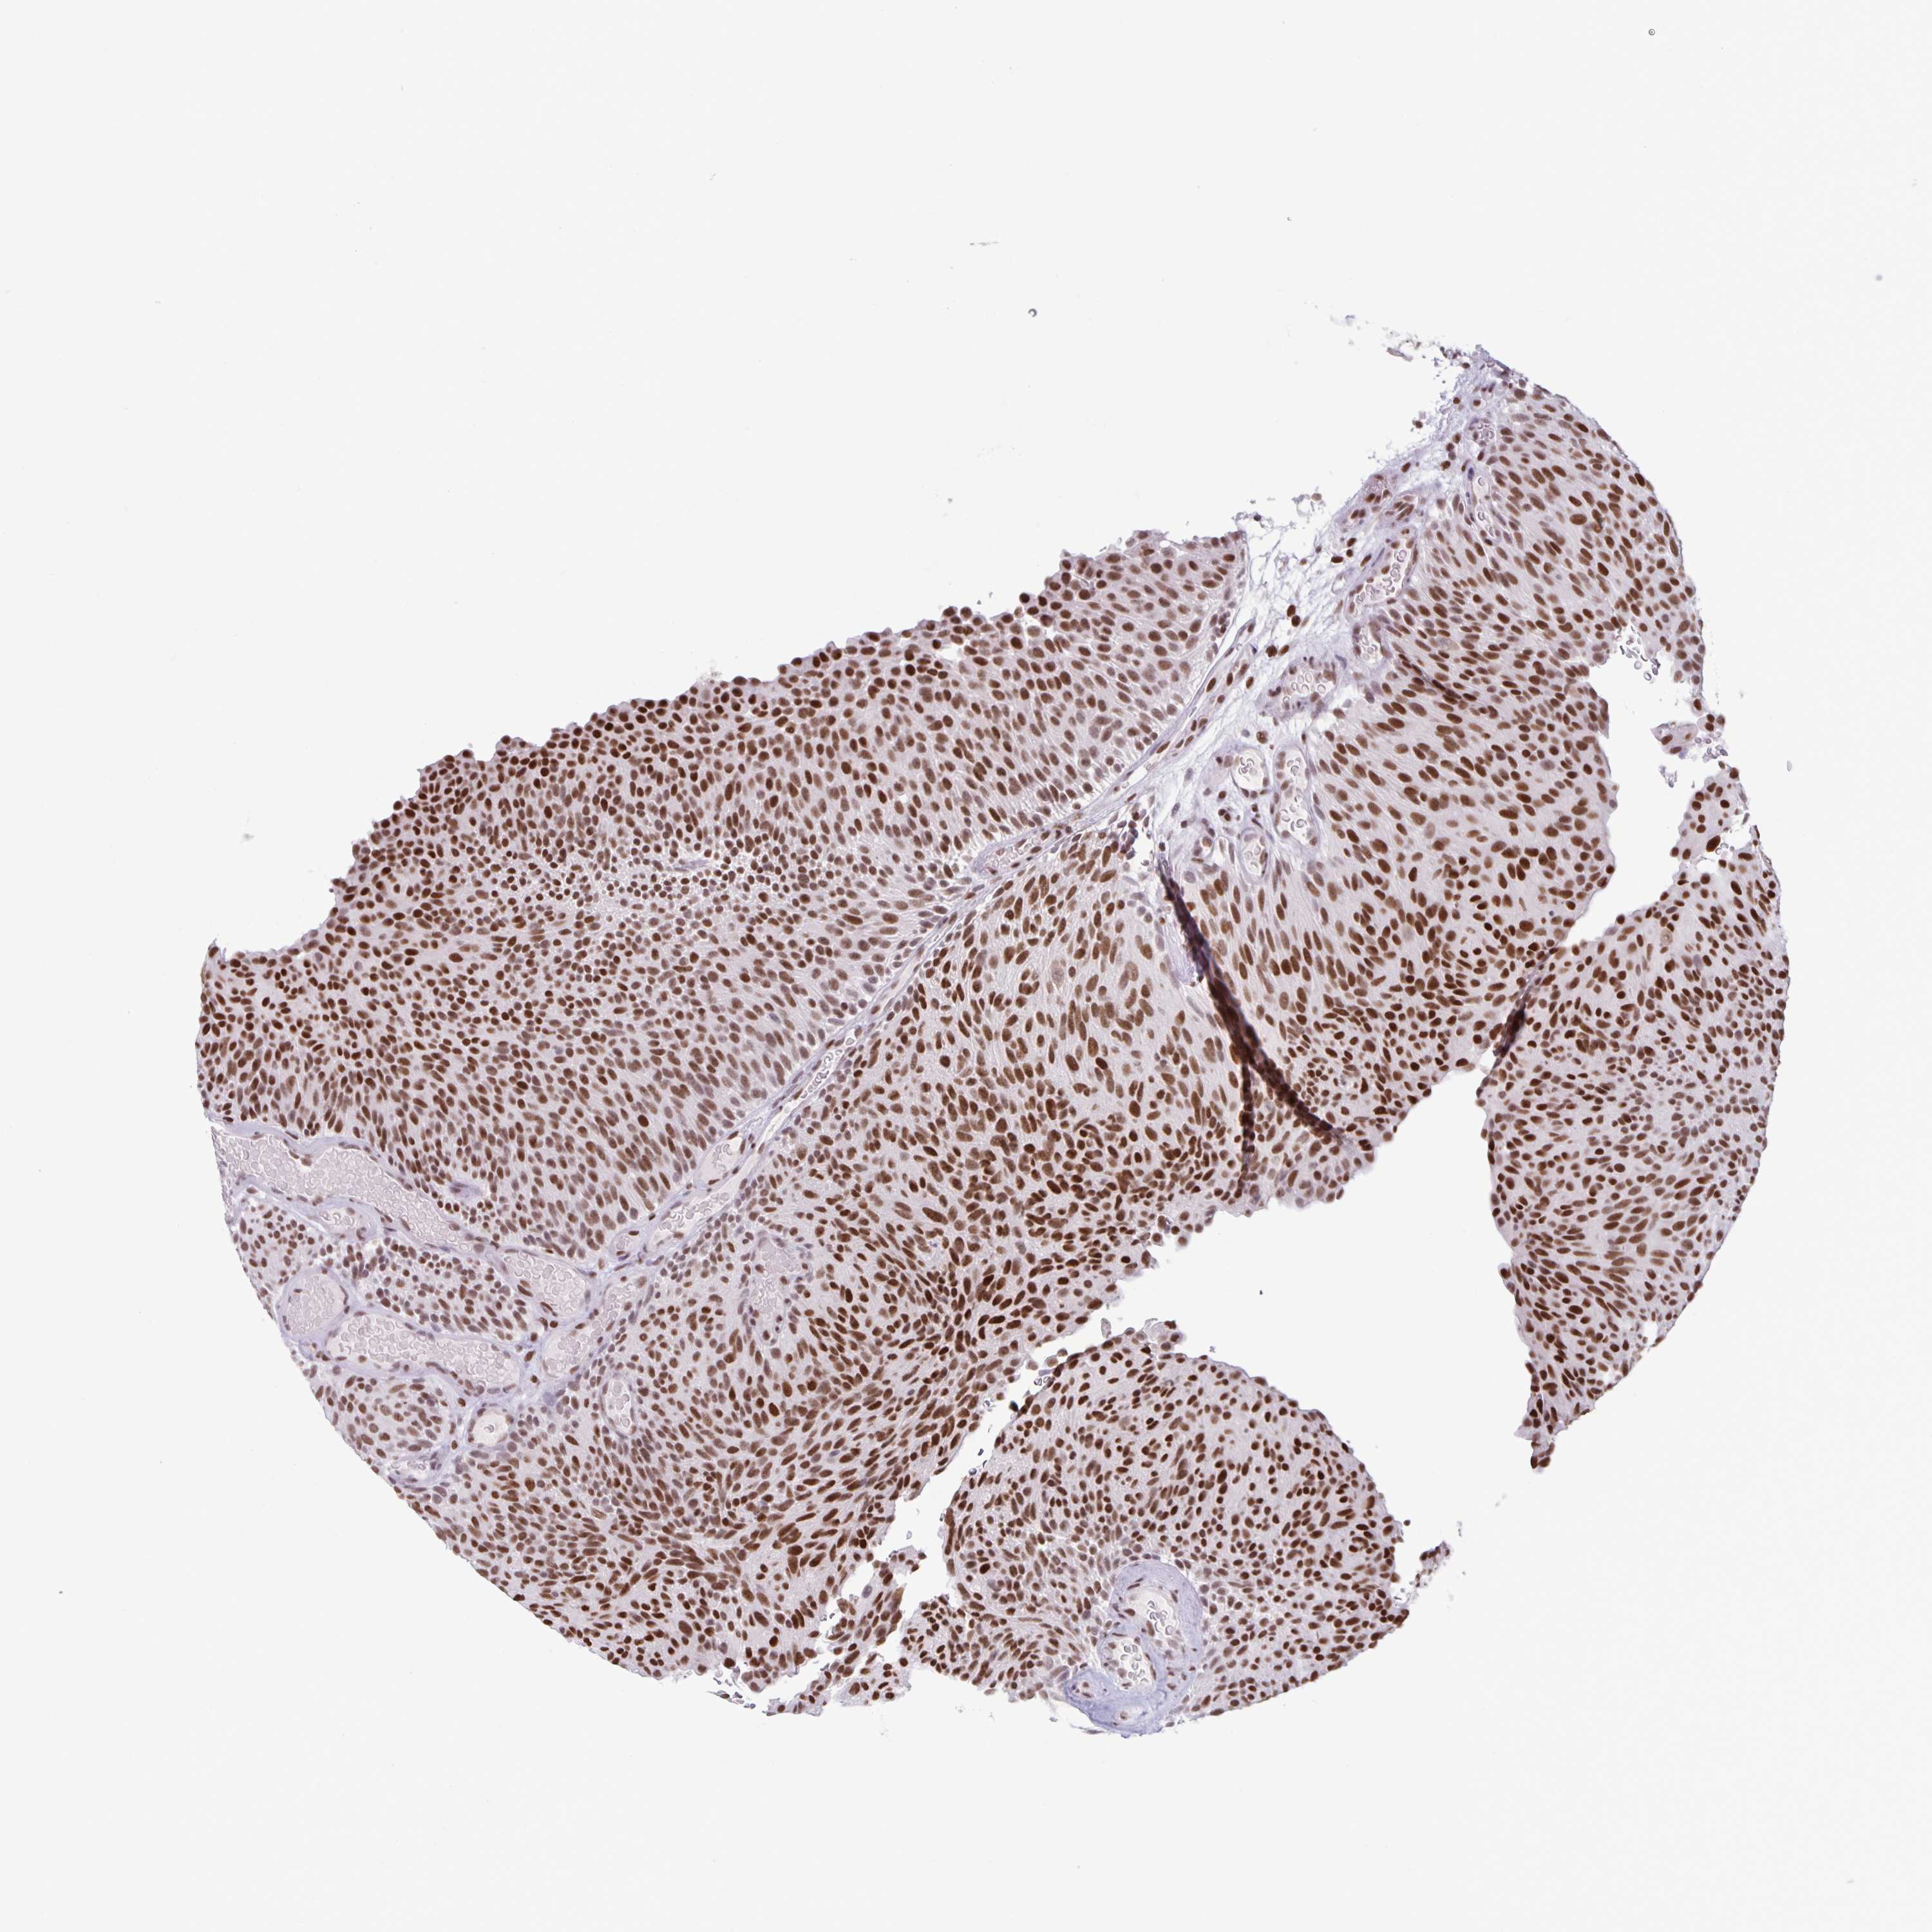

UROTHELIAL CANCER - Protein expressioni

A mouse-over function shows sample information and annotation data. Click on an image to view it in a full screen mode. Samples can be filtered based on level of antibody staining by selecting one or several of the following categories: high, medium, low and not detected. The assay and annotation is described here.

Antibody stainingi

Antibody staining in the annotated cell types in the current human tissue is reported as not detected, low, medium, or high, based on conventional immunohistochemistry profiling in selected tissues. This score is based on the combination of the staining intensity and fraction of stained cells.

Each image is clickable and will lead to virtual microscopy that enables deeper exploration of all samples and also displays staining intensity scores, fraction scores and subcellular localization as well as patient and tissue information for each sample.

Antibody HPA063029

Antibody CAB005268

Staining

High

Medium

Low

Not detected

Intensity

Strong

Moderate

Weak

Negative

Quantity

>75%

75%-25%

<25%

None

Location

Nuclear

Cytoplasmic/membranous

Cytoplasmic/membranous,nuclear

Urothelial carcinoma, High grade